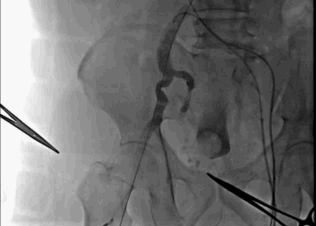

球囊预扩

大小球囊依次预扩

输送系统到位

圈套器snare 协助输送系统安全准确达到预计区域,猪尾主动脉根部造影确认系统和窦底的相对位置,调整重置锚定区